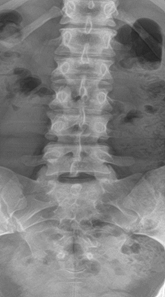

These findings include wedging of greater than 25% of L1 and L2, well-defined endplate concavities at L2 and L4, limbus bone at L5, and disc height narrowing at L1/2 and L2/3 (Figure 3 and 4). If these findings were noted in the thoracic spine, the diagnosis of Scheuermann’s disease would be fairly easy to assume; however, in the presence of a normal thoracic spine and localized abnormality of the lumbar spine, the diagnosis is more complicated.